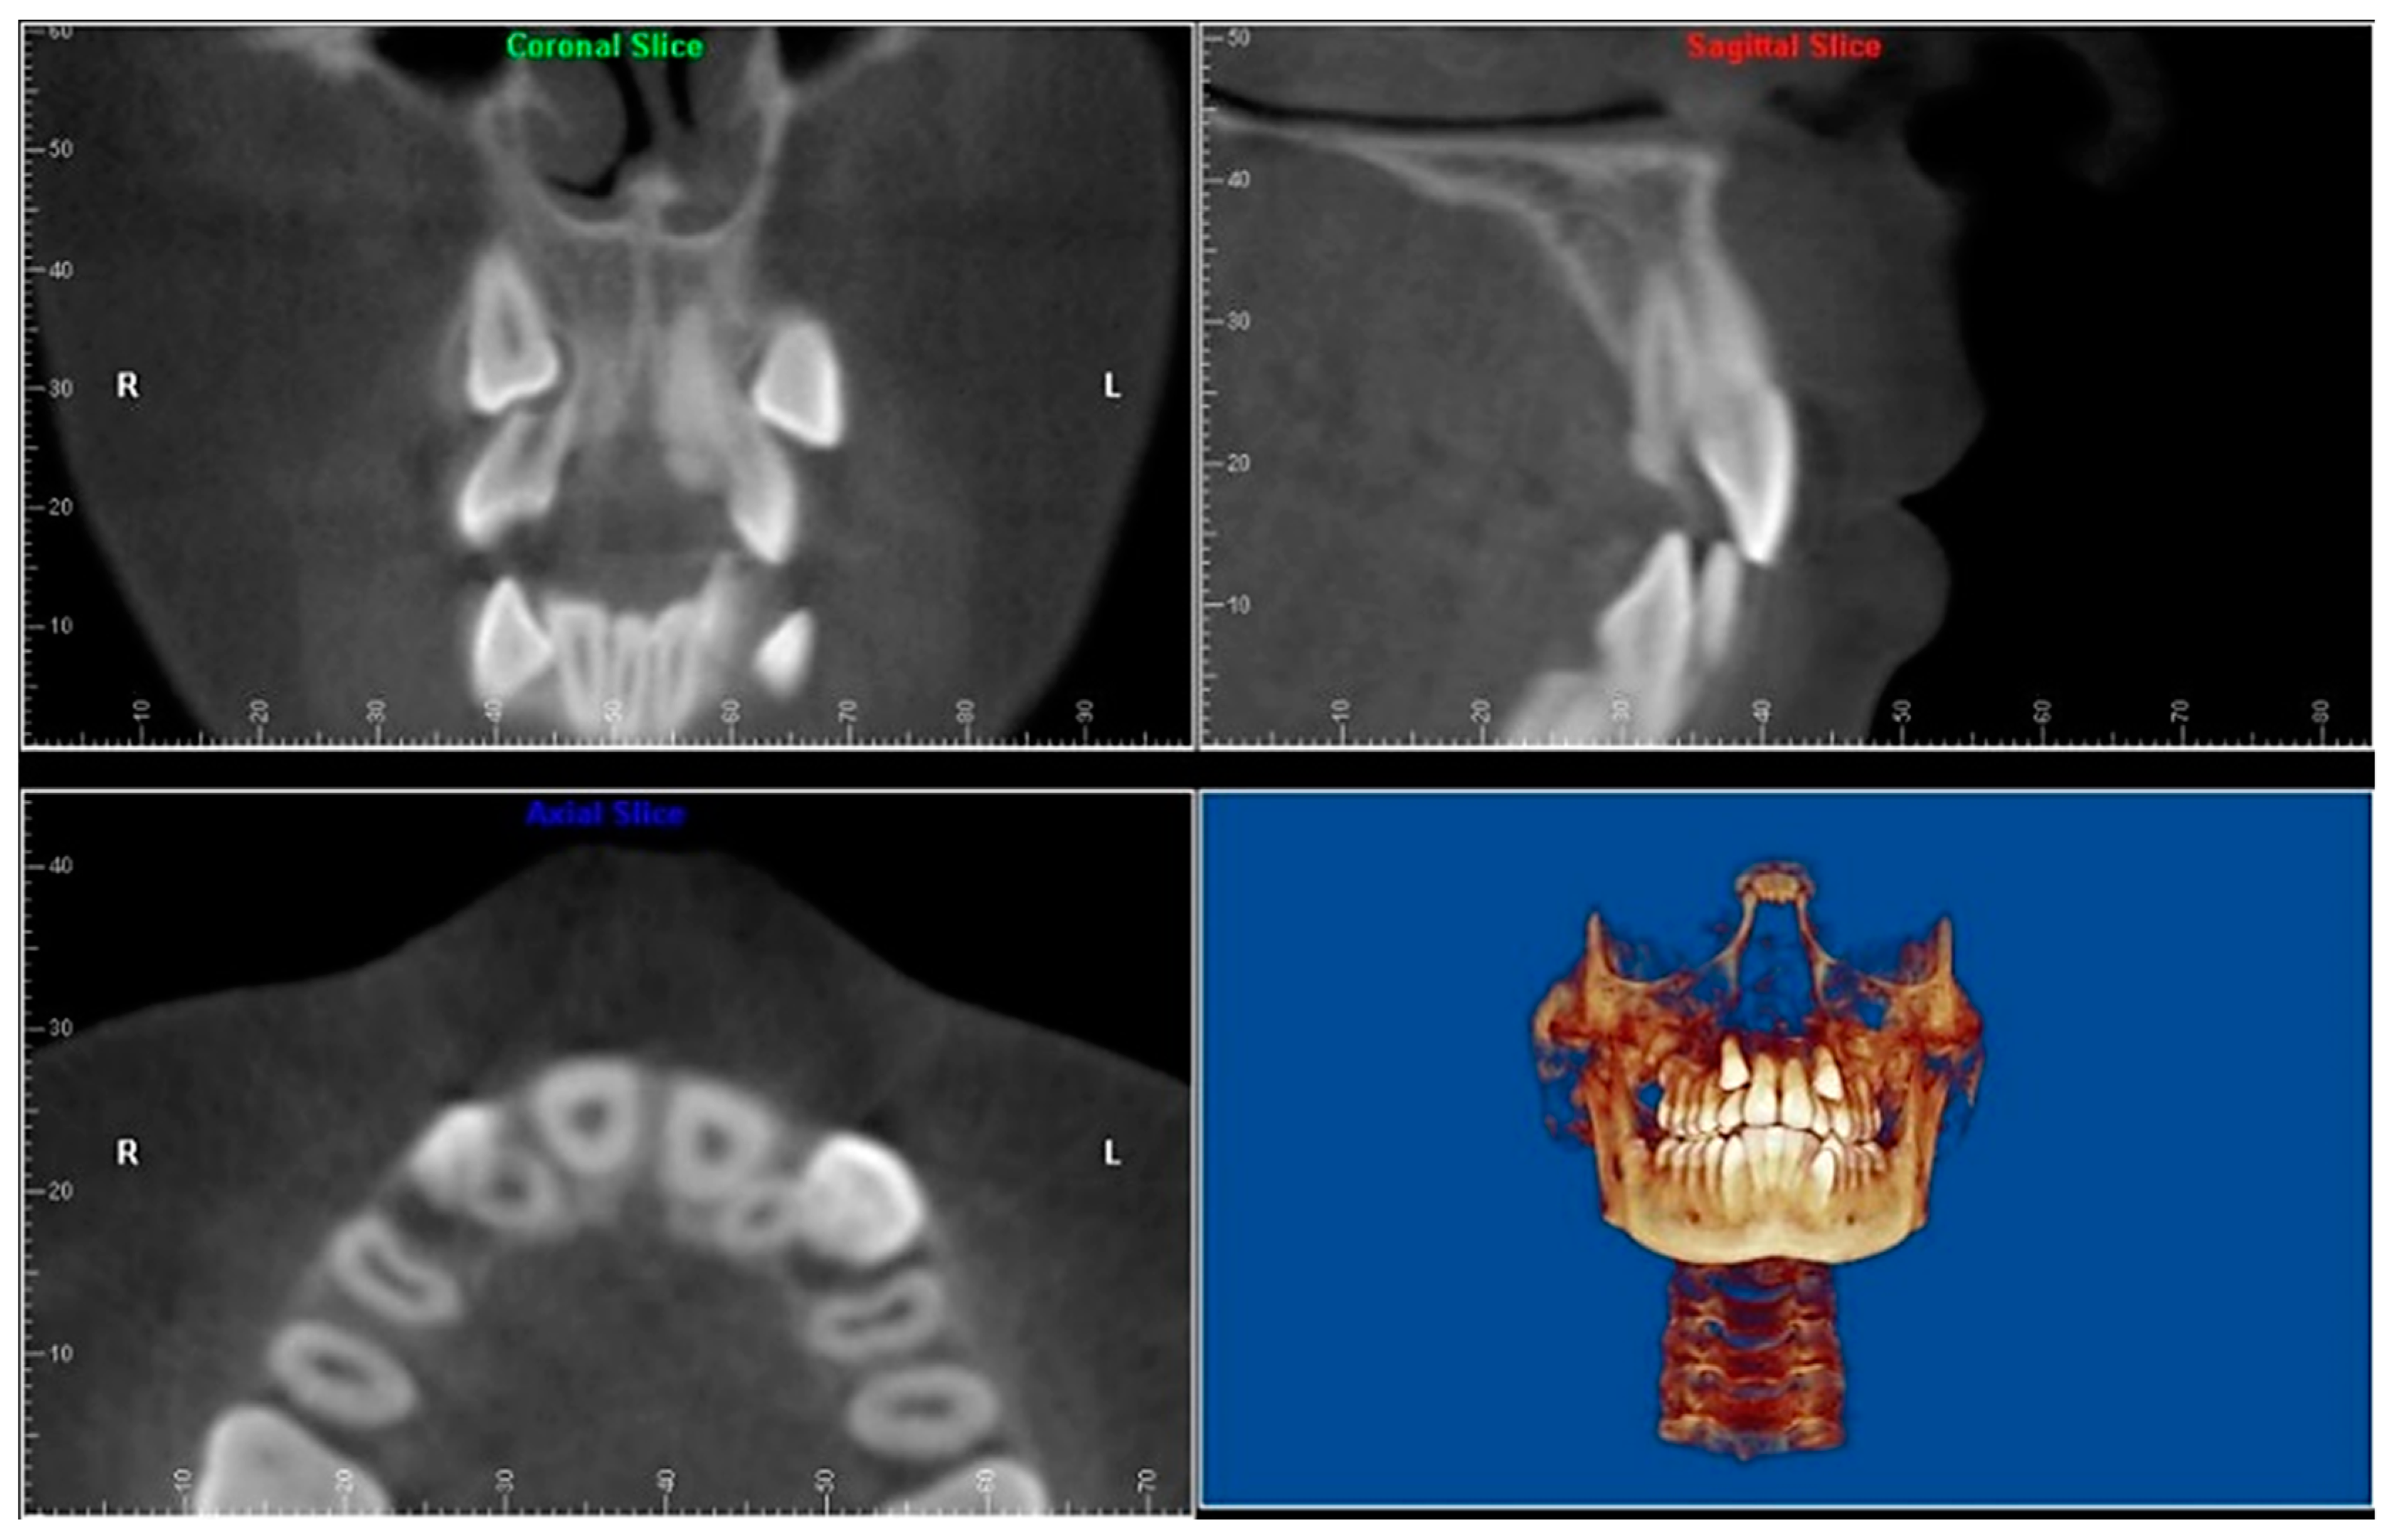

- Evaluation of impacted teeth, a common indication of CBCT in orthodontics. The advantages of CBCT include assessment of the tooth location and position, the stage of development, and status of adjacent teeth. CBCT is justified in these cases, because CBCT has the capability of evaluating the impacted teeth and adjacent structures more accurately than 2D conventional imaging. The benefit–risk ratio is favorable, especially if the CBCT volume is collimated to the impacted tooth. Figure 1, Figure 2, Figure 3 and Figure 4 show an example of impacted maxillary canines, and their proximity to the maxillary lateral incisors. Figure 1 shows an intraoral photograph. The benefit of CBCT acquisition in this case includes the ability to visualize the canines and the lateral incisors in three dimensions, which can be visualized in Figure 2 and Figure 3. In this case, the maxillary right lateral incisor exhibited external root resorption, a finding that would be difficult to see on a conventional 2D panoramic radiograph. Figure 4 shows a Maximum Intensity Projection of a panoramic view derived from the CBCT volume. This unique view is free of magnification, distortion, ghost images, and overlaps frequently seen in conventional 2D panoramic radiography.